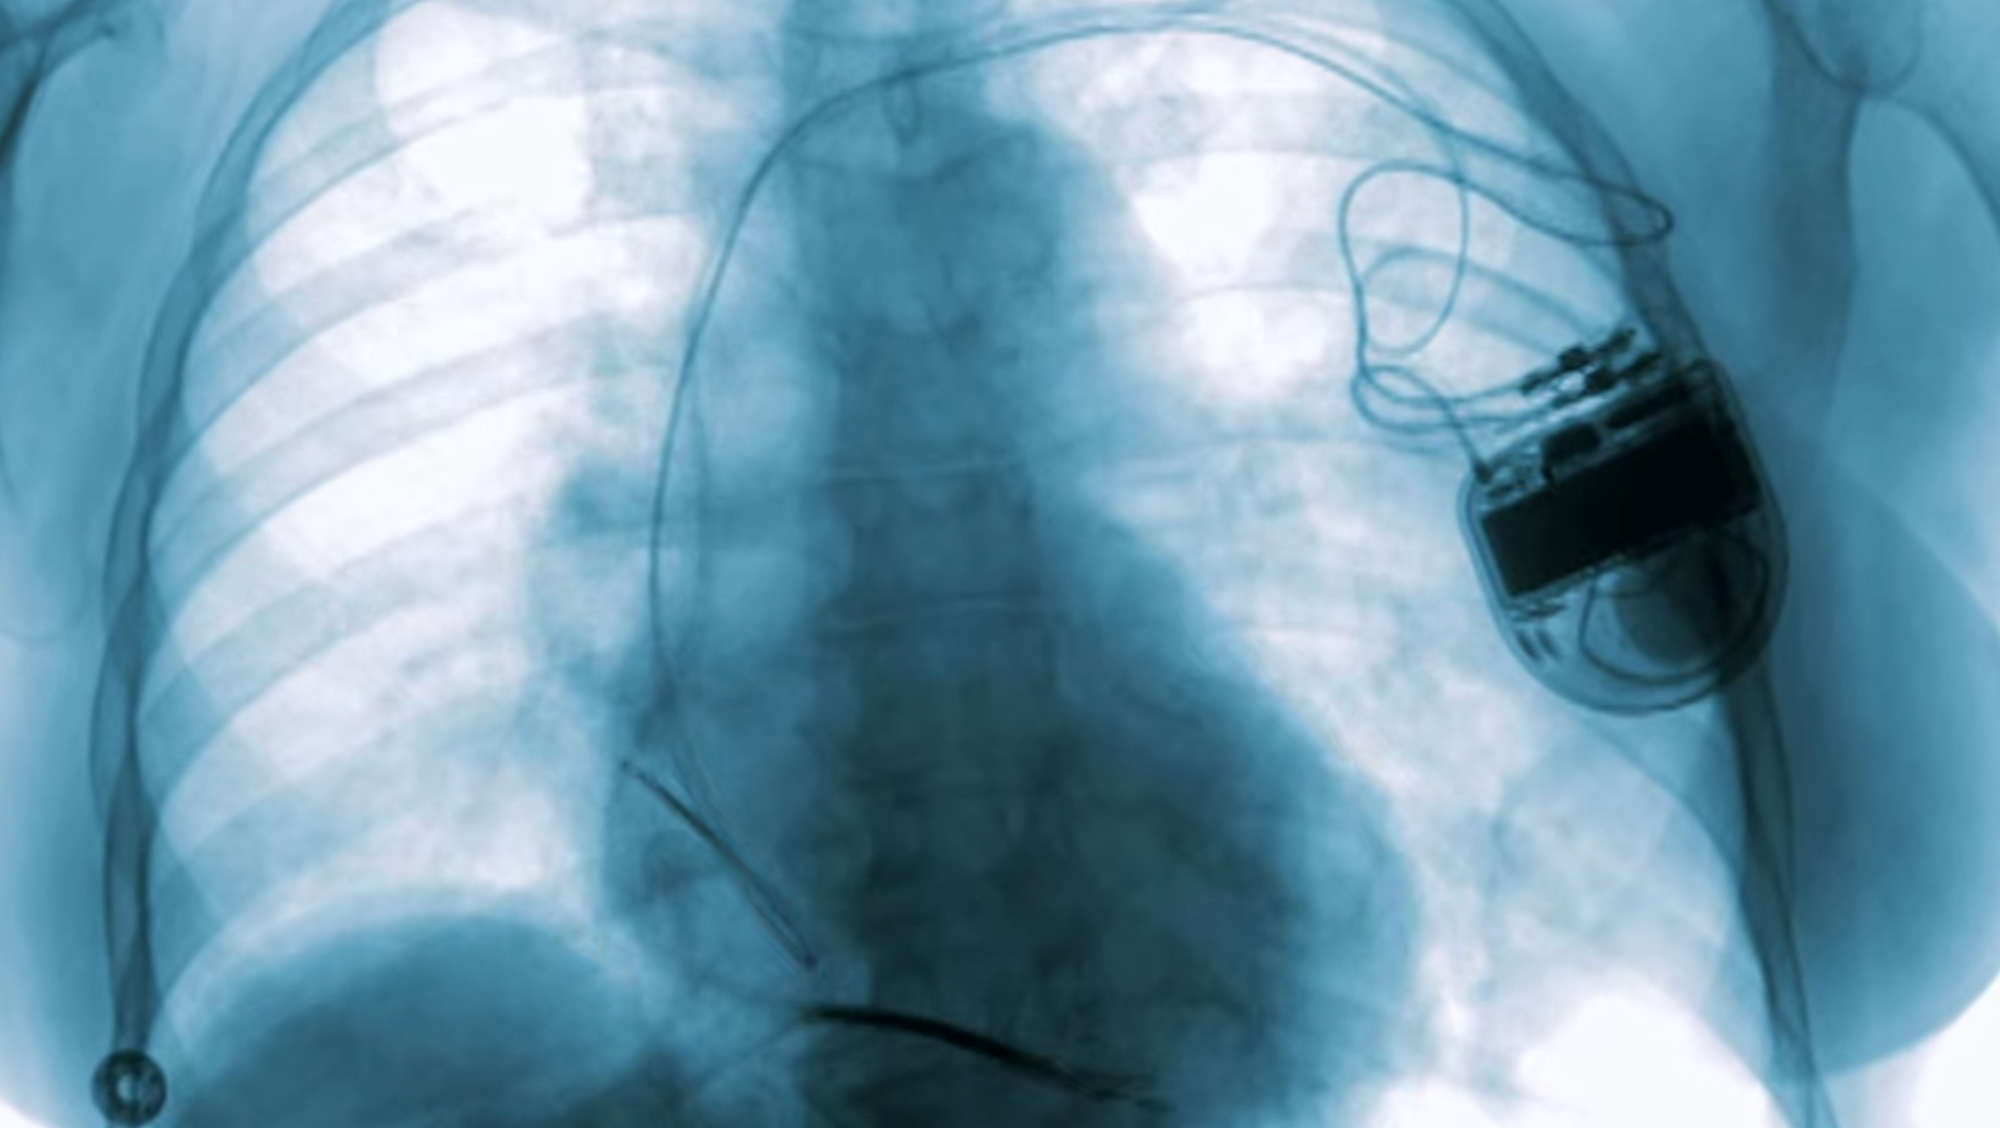

한 여성은 보통 사람보다 심장의 크기가 3배가 되는 비후형심장근육병증을 앓고 있었다. 이 병 때문에 그녀는 마흔에 급사할 가능성이 아주 컸다. 전기 생리학자는 심박조율 제세동기가 있으니 괜찮을 거라고, 전혀 문제없을 거라고 말했다. 이 장치는 코드로 작동하는데, 몇 년 전 임신을 하자 심장이 두근거렸다. 4분의 1 정도의 여성이 임신 후 두근거림 증상을 보이는데, 그것은 지극히 정상적인 증상이다.

하지만 이 장치는 그 자연스러운 증상을 위험하다고 받아들이고 그녀의 심장에 전기 충격을 주었다. 기기 제조업체들이 임산부한테 충격을 주려던 것은 아니었을 것이다. 그런 건 절대 원치 않았을 것이다. 그저 생각을 하지 못했을 뿐이다.